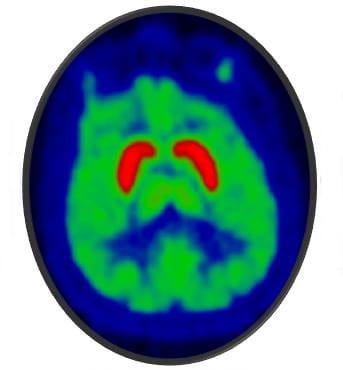

Radiotracers used in PET imaging allow us to see chemical changes in the living human brain, to better understand mental illnesses and aid in developing new treatments. With our new radiotracers, we can identify differences in brain chemistry between people with and without mental illness, understand how medications work and should be dosed, and pinpoint opportunities for developing new treatments.